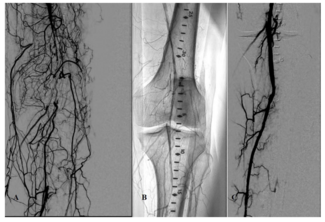

Waheeb John Shammas, BS, MBA, RA, BA; Nicolas W. Shammas, MD, MS, FACC, FSCAI, FACP, FSVM

COVID-19 triggers an inflammatory condition caused by the SARS-Cov-2 virus. Thrombotic events have been commonly described in patients with COVID-19 and they are responsible for a large percentage of deaths seen from this virus.

Dr. Walker comments on Dr. Nicolas Shammas’ article “Management of Thrombotic Occlusion of the Femoropopliteal Artery and Proximal Tibial Vessels in a COVID-19 Patient Using the Auryon Laser.”